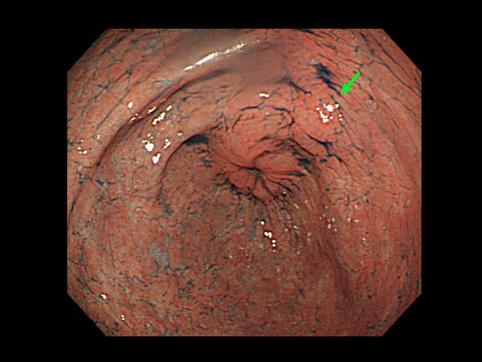

症例提示(所在地,施設名等): 福岡県・ 九州がんセンター

症例登録日 2009/03/31

画像ID:10876

疾患(病理主体)の分類腫瘍様病変/過形成ポリープ

部位(臓器別)胃(部位)/2つ以上

検査方法内視鏡

病変の最大径(ミリ)10〜14